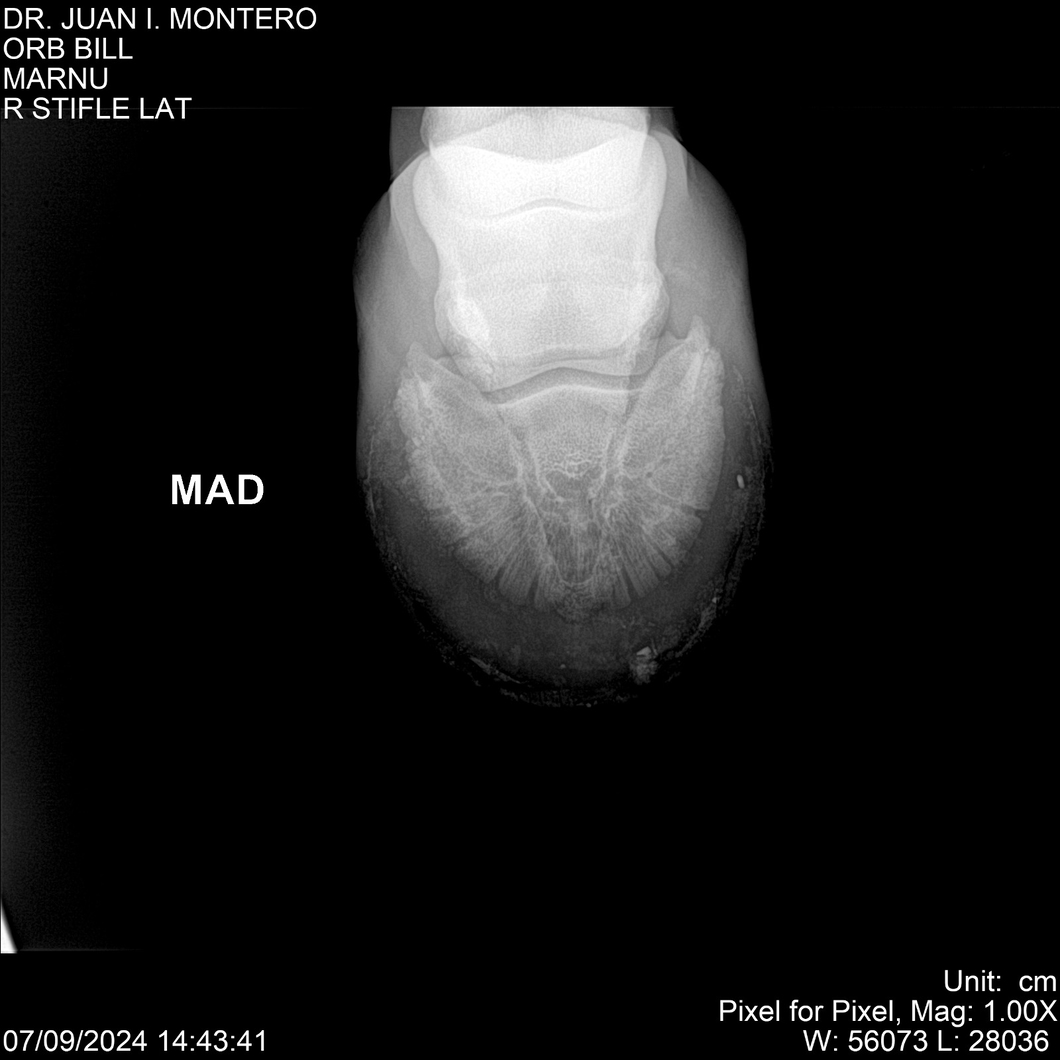

LOTE 7, ORB BILL 🔥 🔥 🔥 Lote Anterior Volver al remate Lote Siguiente Ficha Contacto Montevideo - Ficha del Lote Identificador: #282523 Categoría: Yeguarizos Montevideo - 83 Visualizaciones ClicData Contacto Empresa: Abelenda N. R., Walter Hugo Nombre*: Teléfono* : E-mail* : Mensaje Enviar Registrese gratis Este contenido Exclusivo está disponible sólo para usuarios registrados Ingresar